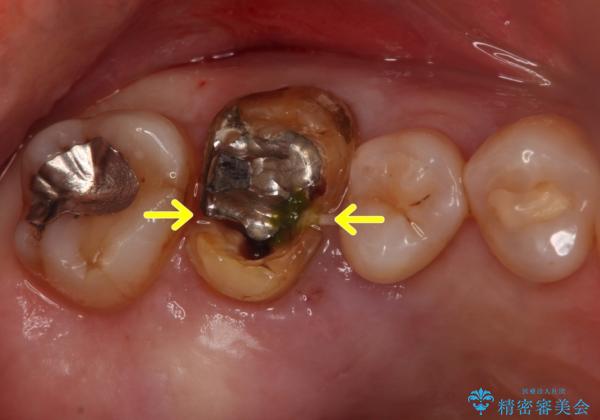

歯の深いところまで割れてしまっている場合は健康な状態での歯の保存ができないため抜歯の適応になります。

今回は抜歯後に骨の補填材を足し、適合の良いブリッジを装着していくこととなりました。